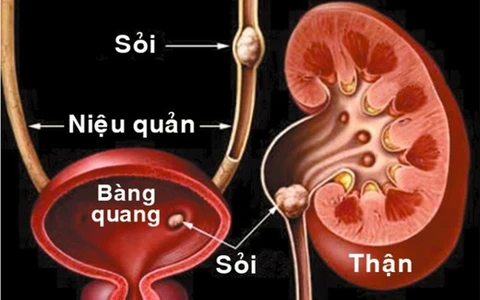

sỏi đường tiết niệu

Tại các trung tâm niệu khoa, bệnh sỏi đường tiết niệu chiếm từ 2/3 đến 3/4 trong các bệnh về đường tiết niệu.

TTO - Khoa ngoại niệu Bệnh viện Nhi đồng 2 TP.HCM trung bình mỗi tháng tiếp nhận 4-5 trẻ mắc sỏi đường tiết niệu. Đáng chú ý, số lượng trẻ mắc sỏi đường tiết niệu năm nay tăng hơn so với những năm trước.